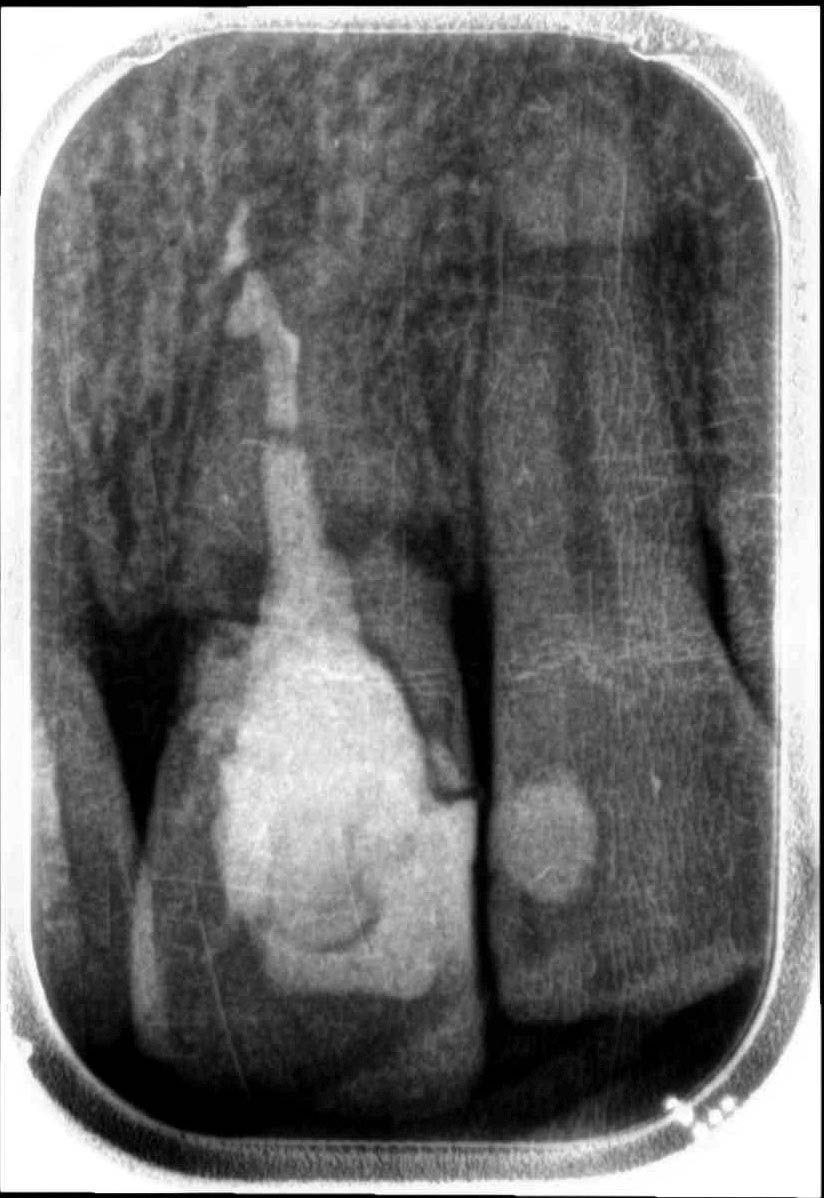

Clinical image and initial radiograph: the fractured on the element 2.1 is noted.